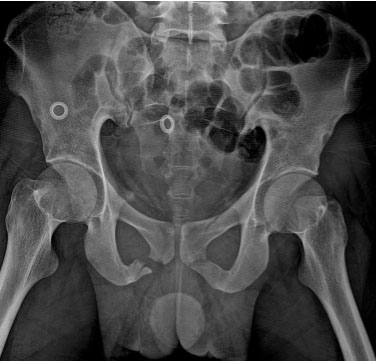

A 23-year-old male presented to the emergency department with complaints of scrotal swelling and pain for three hours due to fall from height on perinium. He had classic signs of a urethral injury and penile fracture. On physical examination he had blood at the meatus, scrotum swelling, butterfly perineal ecchymosis, and he was unable to void (Figure 1). Lab results were within normal values and radiological images done with X-ray confirmed a pelvis fracture (Figure 2), computed tomography (CT) showed right proximal corpora cavernosa and spongiosa ruptures (Figure 3) also there are no other associated organs injuries such as bowel, renal, ureters, and bladder injuries. Foley catheter was succeeded after gentle single attempt, he underwent scrotal exploration for hematoma evacuation (Figure 4) and right proximal corpora cavernosa and spongiosa repair (Figure 5 and Figure 6). During hospital course post-procedure daily dressing, antibiotics, and Foley kept for three weeks then periurethral retrograde urethrogram (RUG) was done outside our hospital without any extravasation. Currently the patient voids freely.

Figure 2: X-ray shows pelvis fracture.